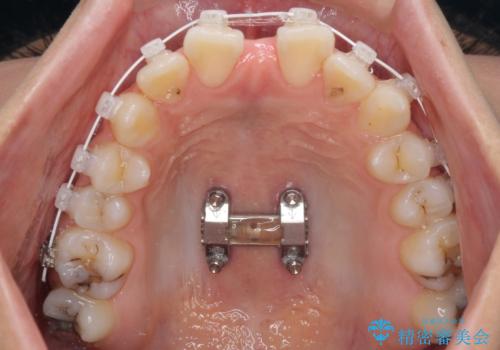

急速拡大装置を用いて上顎骨を側方に拡大し、上顎の叢生を解消するとともに下顎歯列拡大により下顎の叢生も解消することとしました。

急速拡大装置使用直後は著しいスペースが正中に発現するため、ワイヤー矯正を行いますが、今回は治療期間を短くしたいとのことで、上下全体をワイヤー装置にて矯正治療することとしました。